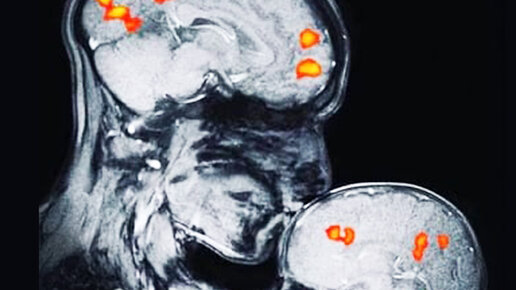

Вот что происходит в мозгу ребенка, когда мама целует его! Изображение узи говорит более тысячи слов

У людей, как и у других млекопитающих сразу после родов, существует „период чувствительности " продолжающийся несколько минут, а может и больше. Развитию правильной связи с матерью во многом способствует контакт кожа к коже в раннем послеродовом периоде. Окситоцин в крови матери еще имеет высокую концентрацию. Именно он, по мнению исследователей, оказывает, помимо прочего, влияние на формирование связей. В первый год жизни ребенок выстраивает с родителями необычайный контакт, поэтому очень важно не потратить это драгоценное время зря...